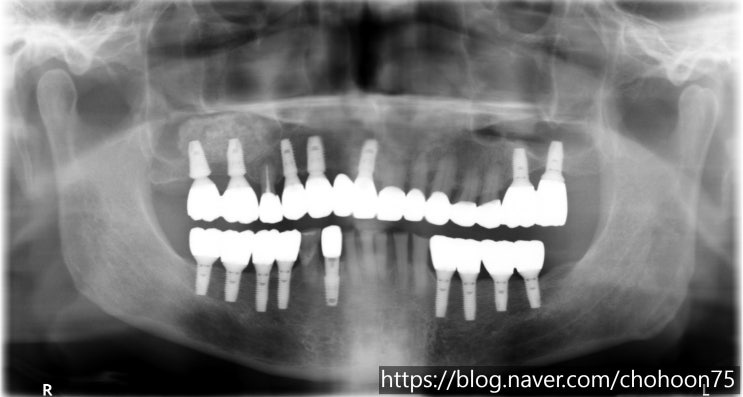

[조훈치과] 다수의 치아 상실 임플란트 치료로 대체

안녕하세요. 조훈 치과입니다. 많은 치아의 임플란트 식립이 필요하다면? 대부분의 치아를 상실하였을 때 ...